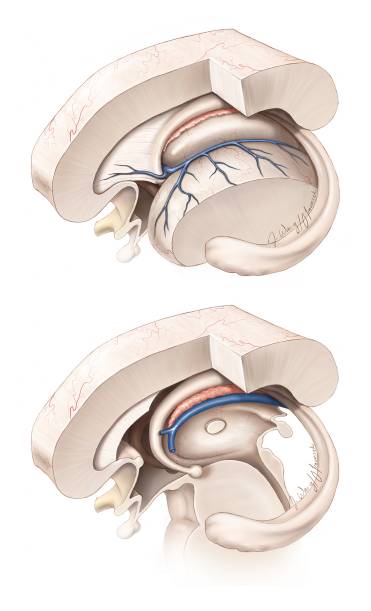

图3. 图示三脑室前部的解剖通道。脑室的大小、因肿瘤所致的室间孔和前脉络裂扩大的程度决定半球间手术通道的侧别。

总之,经胼胝体入路显露了同侧脑室。然后,切断隔静脉与丘纹静脉之间的连接扩大Monro孔。这一操作允许通过分离一小段前脉络膜裂而无需处理丘脑和丘纹静脉就可扩大室间孔。两侧不对称的肿瘤可对侧经室间孔入路(交叉对角线)处理其外侧部分。

沿同侧大脑内静脉内壁分离并向后延伸,进一步扩大进入三脑室的手术通道,直至显露双侧大脑内静脉,该空间足以显露病变的后极。